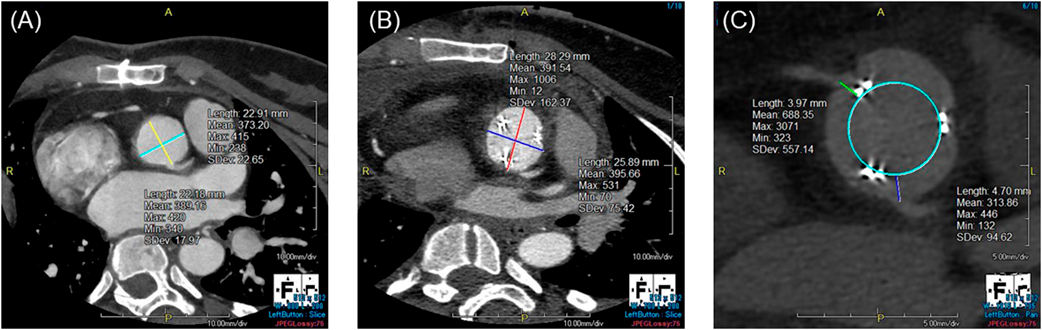

At the time of surgery, the patient was 135 cm in height and weighed 38.0 kg. Chest X-ray showed cardiomegaly and pulmonary venous congestion. Brain nitric peptide level was 66.8 pg/mL. Echocardiography (Fig. 1) showed a left ventricular end-diastolic diameter of 43 mm, left ventricular ejection fraction of 67%, severe AS (aortic valve area, 0.72 cm2), peak velocity of 4.6 m/s, peak pressure gradient of 84 mmHg, and severe AR. The pulmonary valve was normal in diameter with no pulmonary regurgitation noted. On contrast-enhanced computed tomography (CT), diameters of the aortic annulus, the sinus of Valsalva, the sino-tubular junction, and the ascending aorta were 19.0 mm, 22.9 mm×22.2 mm, 19.3 mm×22.7 mm, and 28.3 mm, respectively. The right and the left coronary arteries took off 15.5 mm and 15.1 mm above the ventriculo-arterial junction, respectively.

Fig. 1 Preoperative echocardiography

(A) Parasternal long axis view: Thickened aortic valve (white arrow) and thickened left ventricular wall. (B) Apical long axis view: Severe aortic regurgitation. (C) Parasternal short axis view: Thickened aortic valve (white arrow). (D) Parasternal short axis view: Severe aortic stenosis (aortic valve area, 0.72 cm2). (E) Parasternal short axis view: Severe aortic regurgitation (a jet through the center).